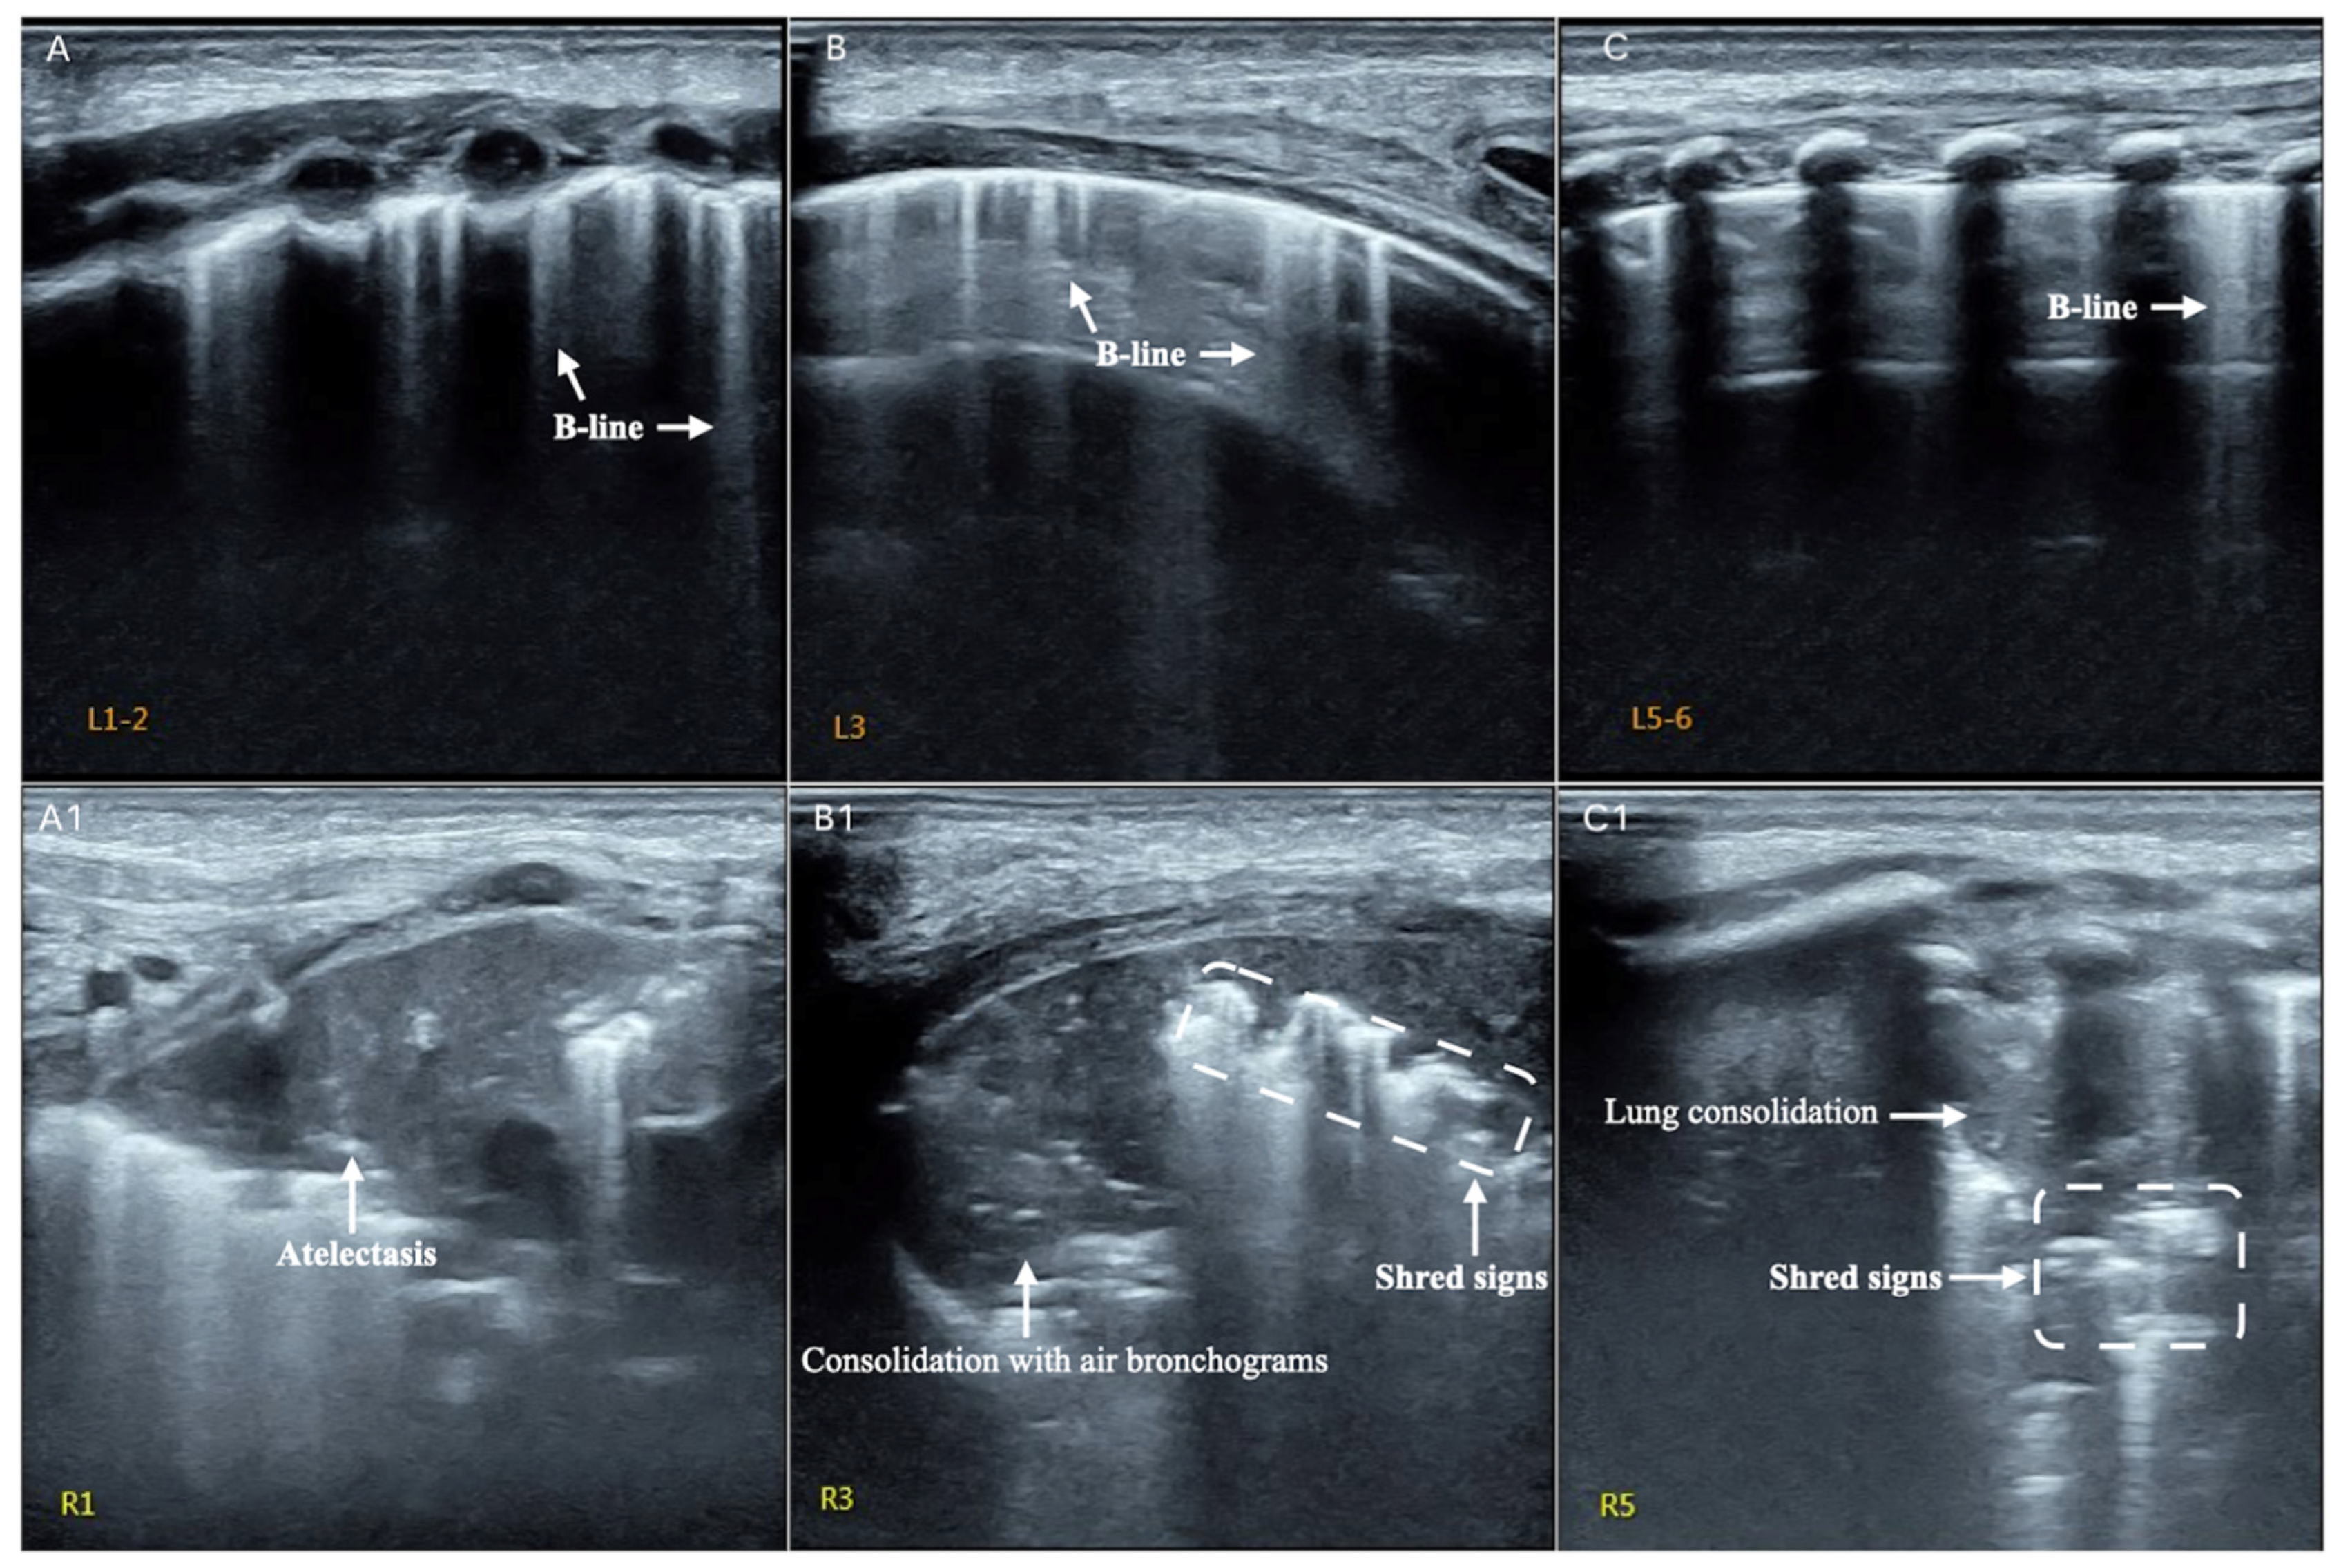

3.3. LUS Findings of FP

3.4. Typical Case Presentations